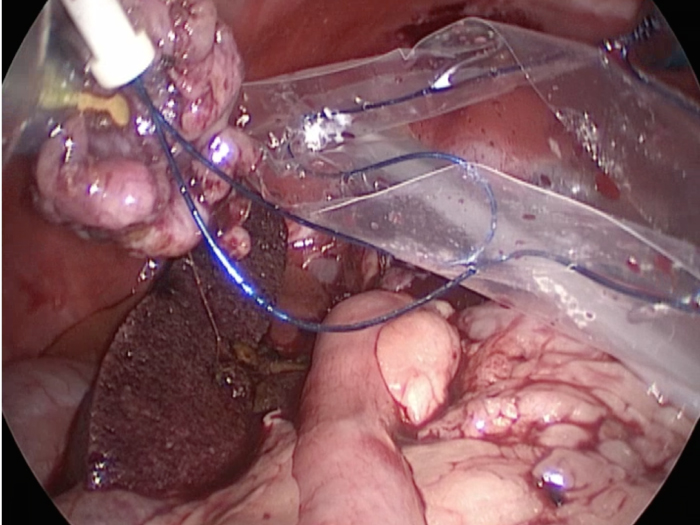

体の外に出すためお腹の中で袋に入れていきます。

このときに胆嚢と一緒にクリップやガーゼも回収します。

そしてお腹の中をきれいにしていきます。

回収袋にいれて体外に摘出していきます。

回収袋にいれて終わりになります。